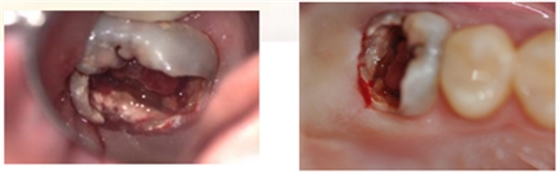

7、初步恢复牙体完整性后上橡皮障,开髓,3% NaClO冲洗,揭除髓顶,修整开髓洞形,去除髓腔牙髓组织。

8、定位根管口后,8#K锉结合根管冠方预敞,逐步探查,四根管通畅。因操作时间过长,未作根管预备,氢氧化钙糊剂暂封根管一周,玻璃离子暂封。

复诊过程

复诊:患者无不适,局麻下上橡皮障,去除暂封材料,结合3% NaClO冲洗,pathfile建立通路,TFA机用镍钛系统根管机械预备。根管荡洗,17%EDTA 溶液,生理盐水终末冲洗,因操作时间时间过长,氢氧化钙糊剂根管封药,玻璃离子暂封。